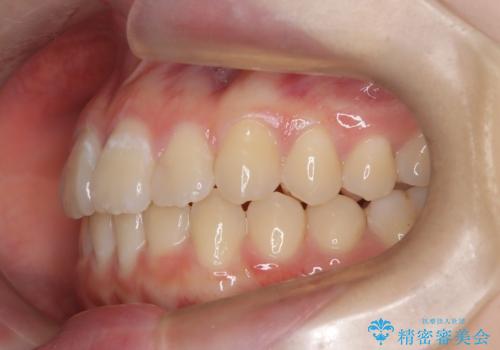

- 前歯のガタツキが気になるとのことで来院されました。

前歯のガタツキに加え、奥歯の噛み合わせにも問題があったため、マウスピース矯正で治療し改善しました。